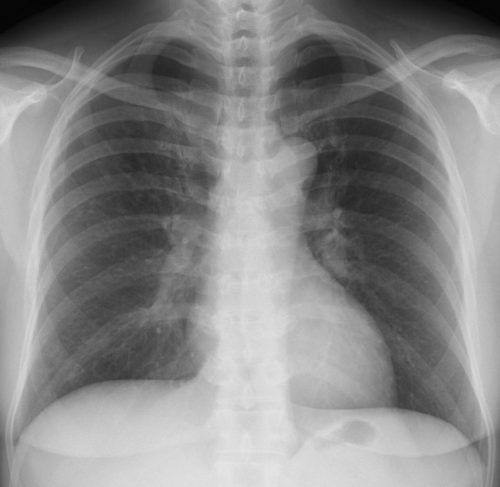

外来でみるクラミジア肺炎

【クラミジア肺炎】